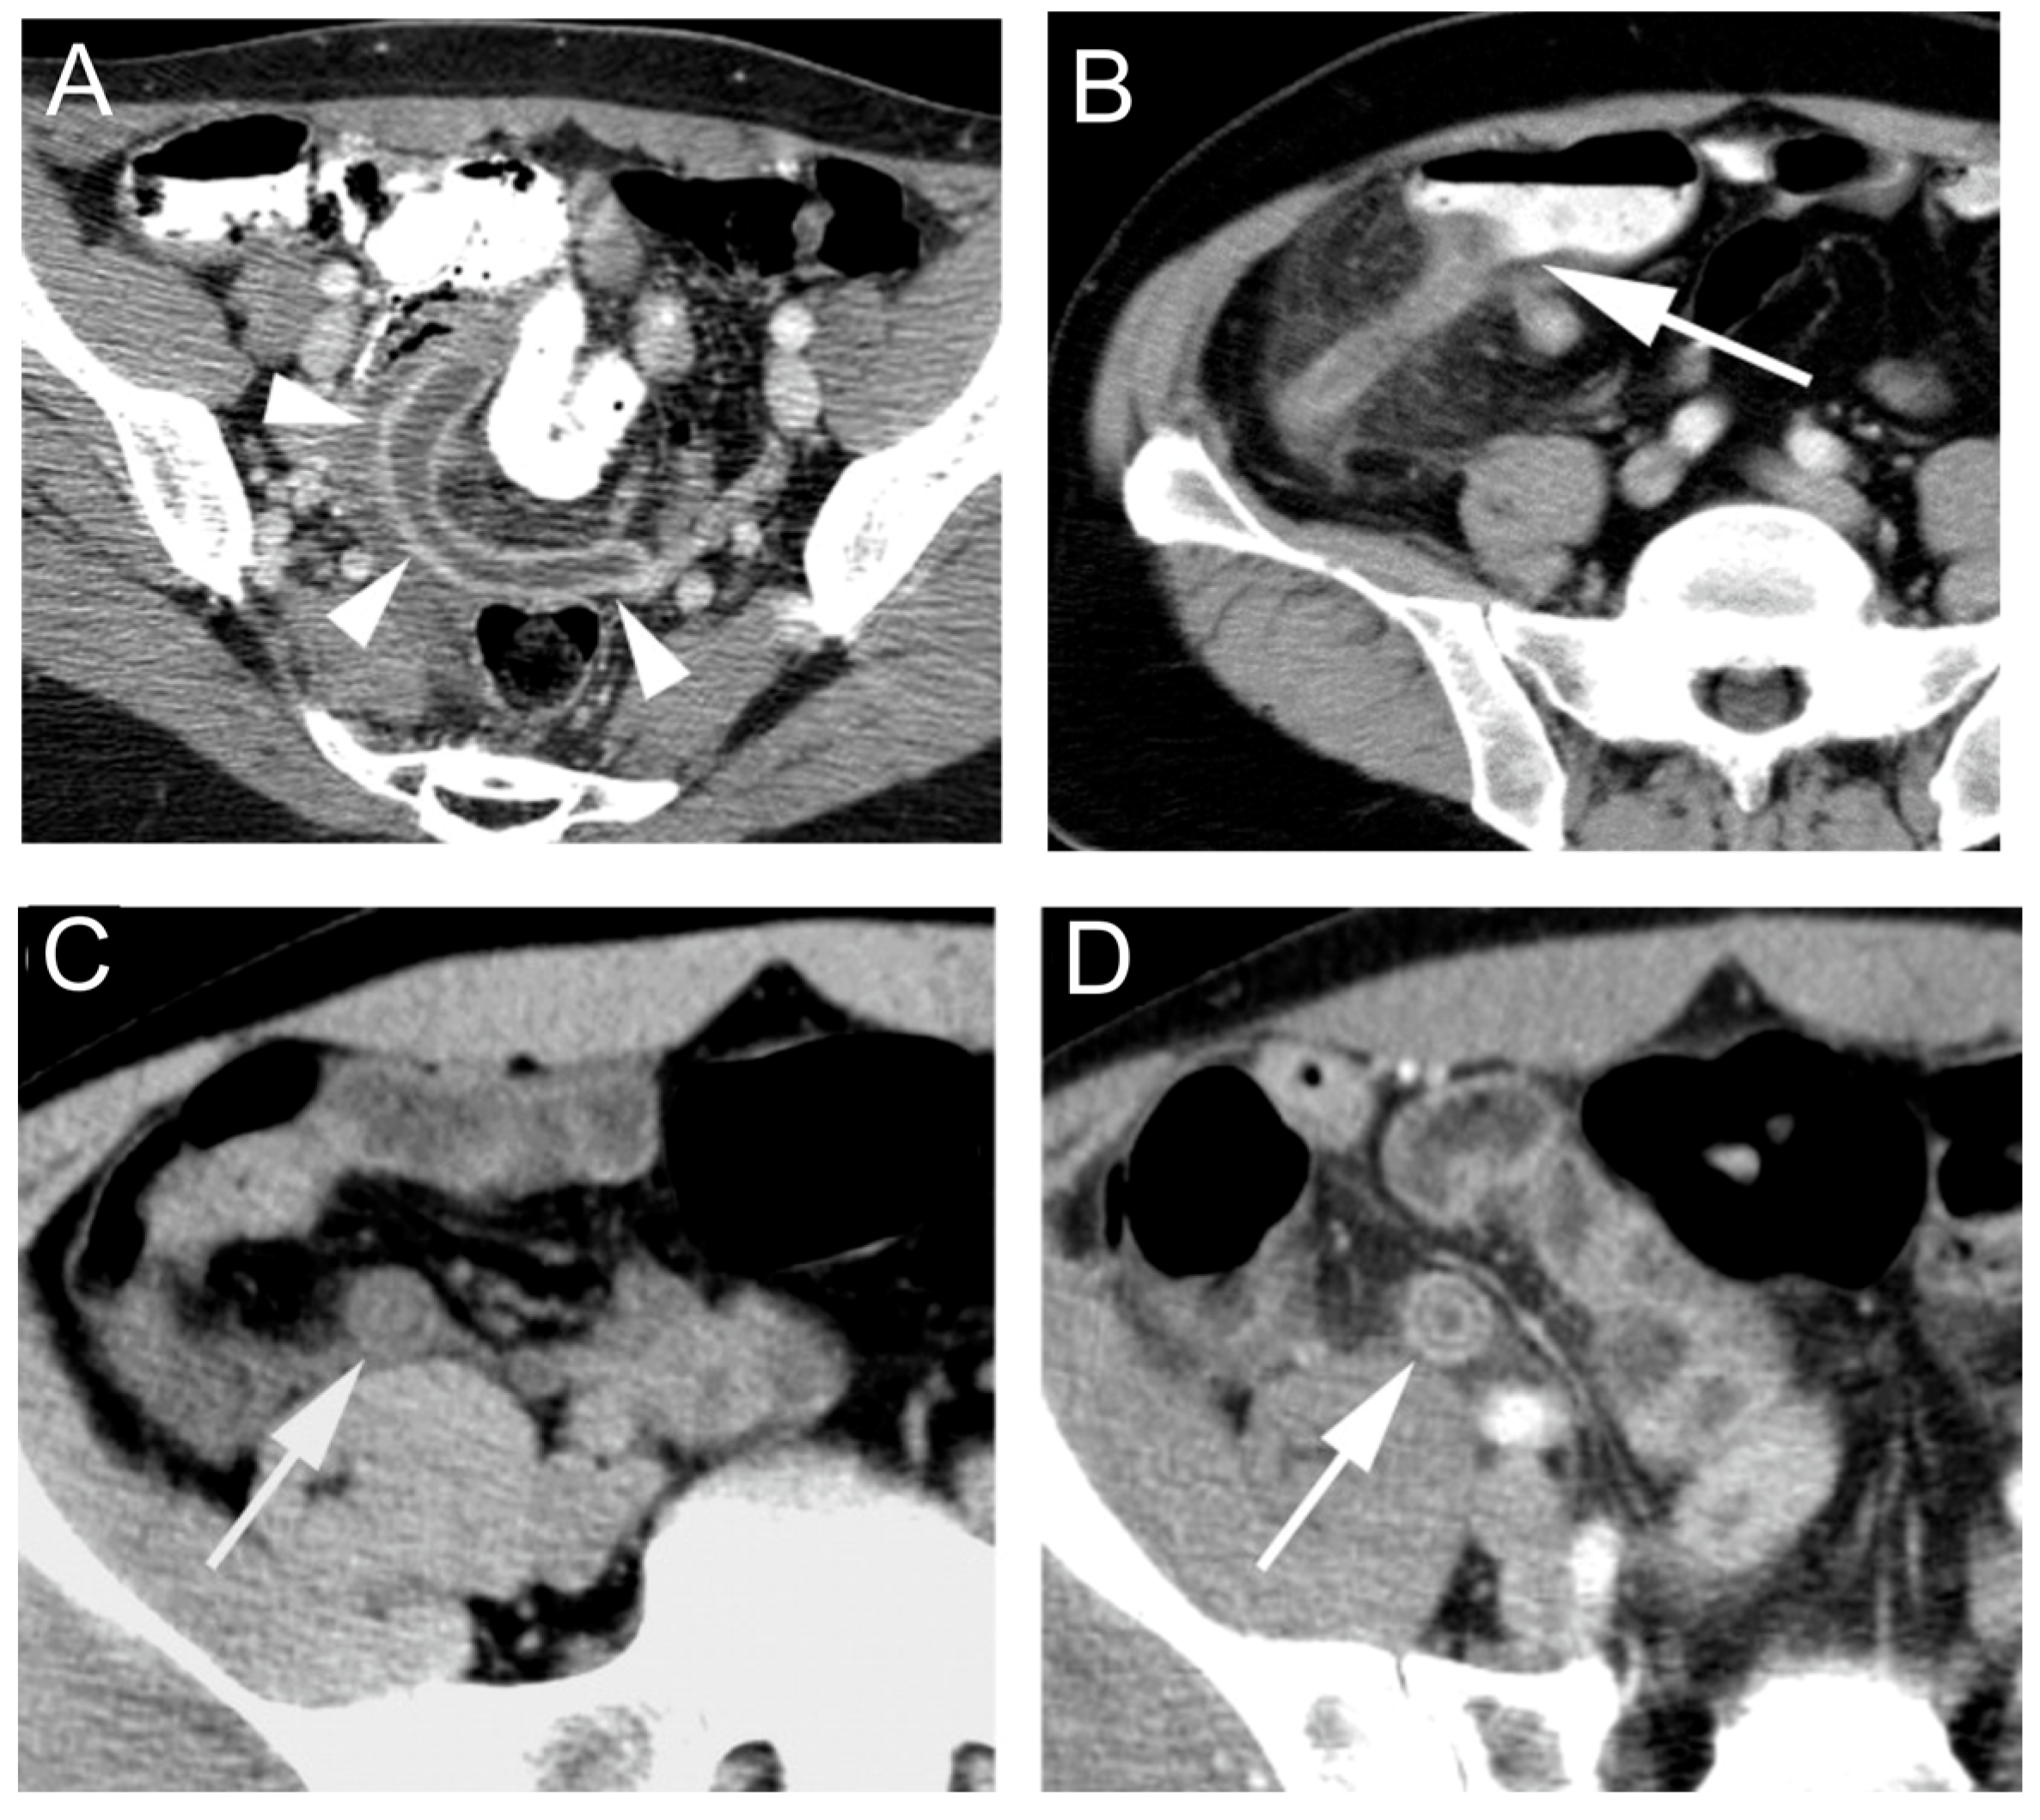

- Monsonis, B.; Mandoul, C.; Millet, I.; Taourel, P. Imaging of appendicitis: Tips and tricks. Eur. J. Radiol. 2020, 130, 109165. [Google Scholar] [CrossRef]

- Pinto Leite, N.; Pereira, J.M.; Cunha, R.; Pinto, P.; Sirlin, C. CT evaluation of appendicitis and its complications: Imaging techniques and key diagnostic findings. AJR Am. J. Roentgenol. 2005, 185, 406–417. [Google Scholar] [CrossRef]

- Brown, M.A. Imaging Acute Appendicitis. Semin. Ultrasound CT MR. 2008, 29, 293–307. [Google Scholar] [CrossRef]

- Gaskill, C.E.; Simianu, V.V.; Carvell, J.; Hippe, D.S.; Bhargava, P.; Flum, D.R.; Davidson, G.H. Use of Computed Tomography to Determine Perforation in Patients with Acute Appendicitis. Curr. Probl. Diagn. Radiol. 2018, 47, 6–9. [Google Scholar] [CrossRef]